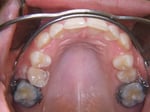

Den weitaus grössten Anteil der Gebissfehlstellungen macht die relative Unterkieferrücklage (Distalbiss) aus. Ist diese relativ gering oder wenn im Grunde eine relative Oberkiefervorlage besteht, kommt oft ein so genannter Headgear (auch salopp „Nachtspange“) zum Einsatz. Auf den ersten oberen grossen Stockzähnen werden 2 festsitzende Bänder zementiert, auf denen der Patient selber am Abend denn Headgearbogen befestigen kann (siehe Bild ganz rechts). Die Aussenarme des Headgearbogens führen auf die Wangenaussenseite, wo die Kopfkappe mit Zug gegen hinten eingehängt wird. So können einerseits die oberen Stockzähne nach hinten bewegt oder an einer Vorwanderung gehindert werden, andererseits wird gleichzeitig auch die wachstumsbedingte Oberkiefervorverlagerung verlangsamt. Dies bietet dem Unterkiefer die Gelegenheit, wachstumsmässig „aufzuholen“. Da der Headgear Einflüsse auf das ganze Kausystem wie auch den Schädel hat, gehört er in die Hände des Spezialisten für Kieferorthopädie, der die Wirkung genau zu dosieren und eventuelle Nebenwirkungen zu verhindern weiss. Der Headgear wird meist nachts getragen, weshalb er oft salopp „Nachtspange“ genannt wird. Wir verwenden die neueste Weiterentwicklung des Headgear, genannt Smartgear. Dieser ist mit einem Mikrochip ausgerüstet und kann die Tragzeit überwachen. Die Kinder werden zur Mitarbeit motiviert, was ein besseres und schnelleres Erreichen des Behandlungsziels ermöglicht.